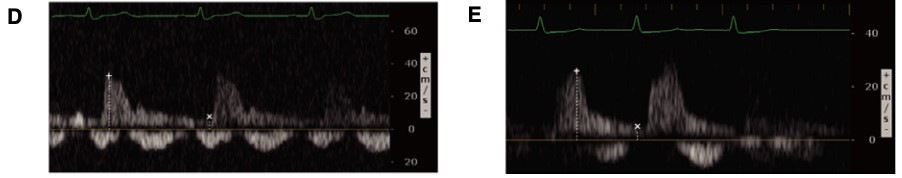

Conversely, renal venous flow remains a more specific marker for renal vein congestion and renosarca as it allows us to assess venous congestion within the venous system itself. As right atrial pressures increase, similar in nature to the hepatic vein, the normal continuous intra-renal venous doppler pattern (Figure 5) transitions to an interrupted biphasic pattern (Figure 8A), and ultimately to a primarily diastolic venous flow pattern (Figure 8B). This remains physiologically similar to our understanding of the hepatic venous waveforms: as right atrial pressures rise; the systolic venous flow will gradually decrease until a primary diastolic venous flow is present. At this point, the venous system loses its ability to compensate for increased fluid. When compared to hepatic venous flow, renal flow provides two major advantages: an ability to easily determine systolic and diastolic flow and being more specific to renal venous congestion.

Figure 8. Abnormal renal vein Doppler6

(Reproduced with permission)

A: Biphasic systolic and diastolic venous flow

B: Monophasic diastolic venous flow